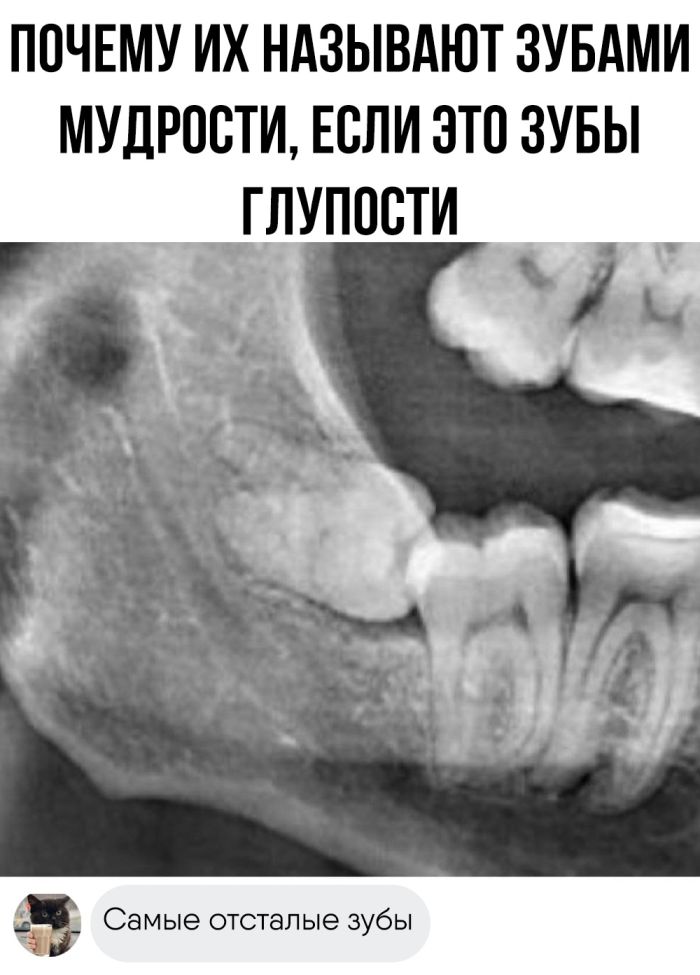

Юмор Веселые картинки и мемы с надписями: заряд позитива и хорошего настроения на весь день (25 фото)